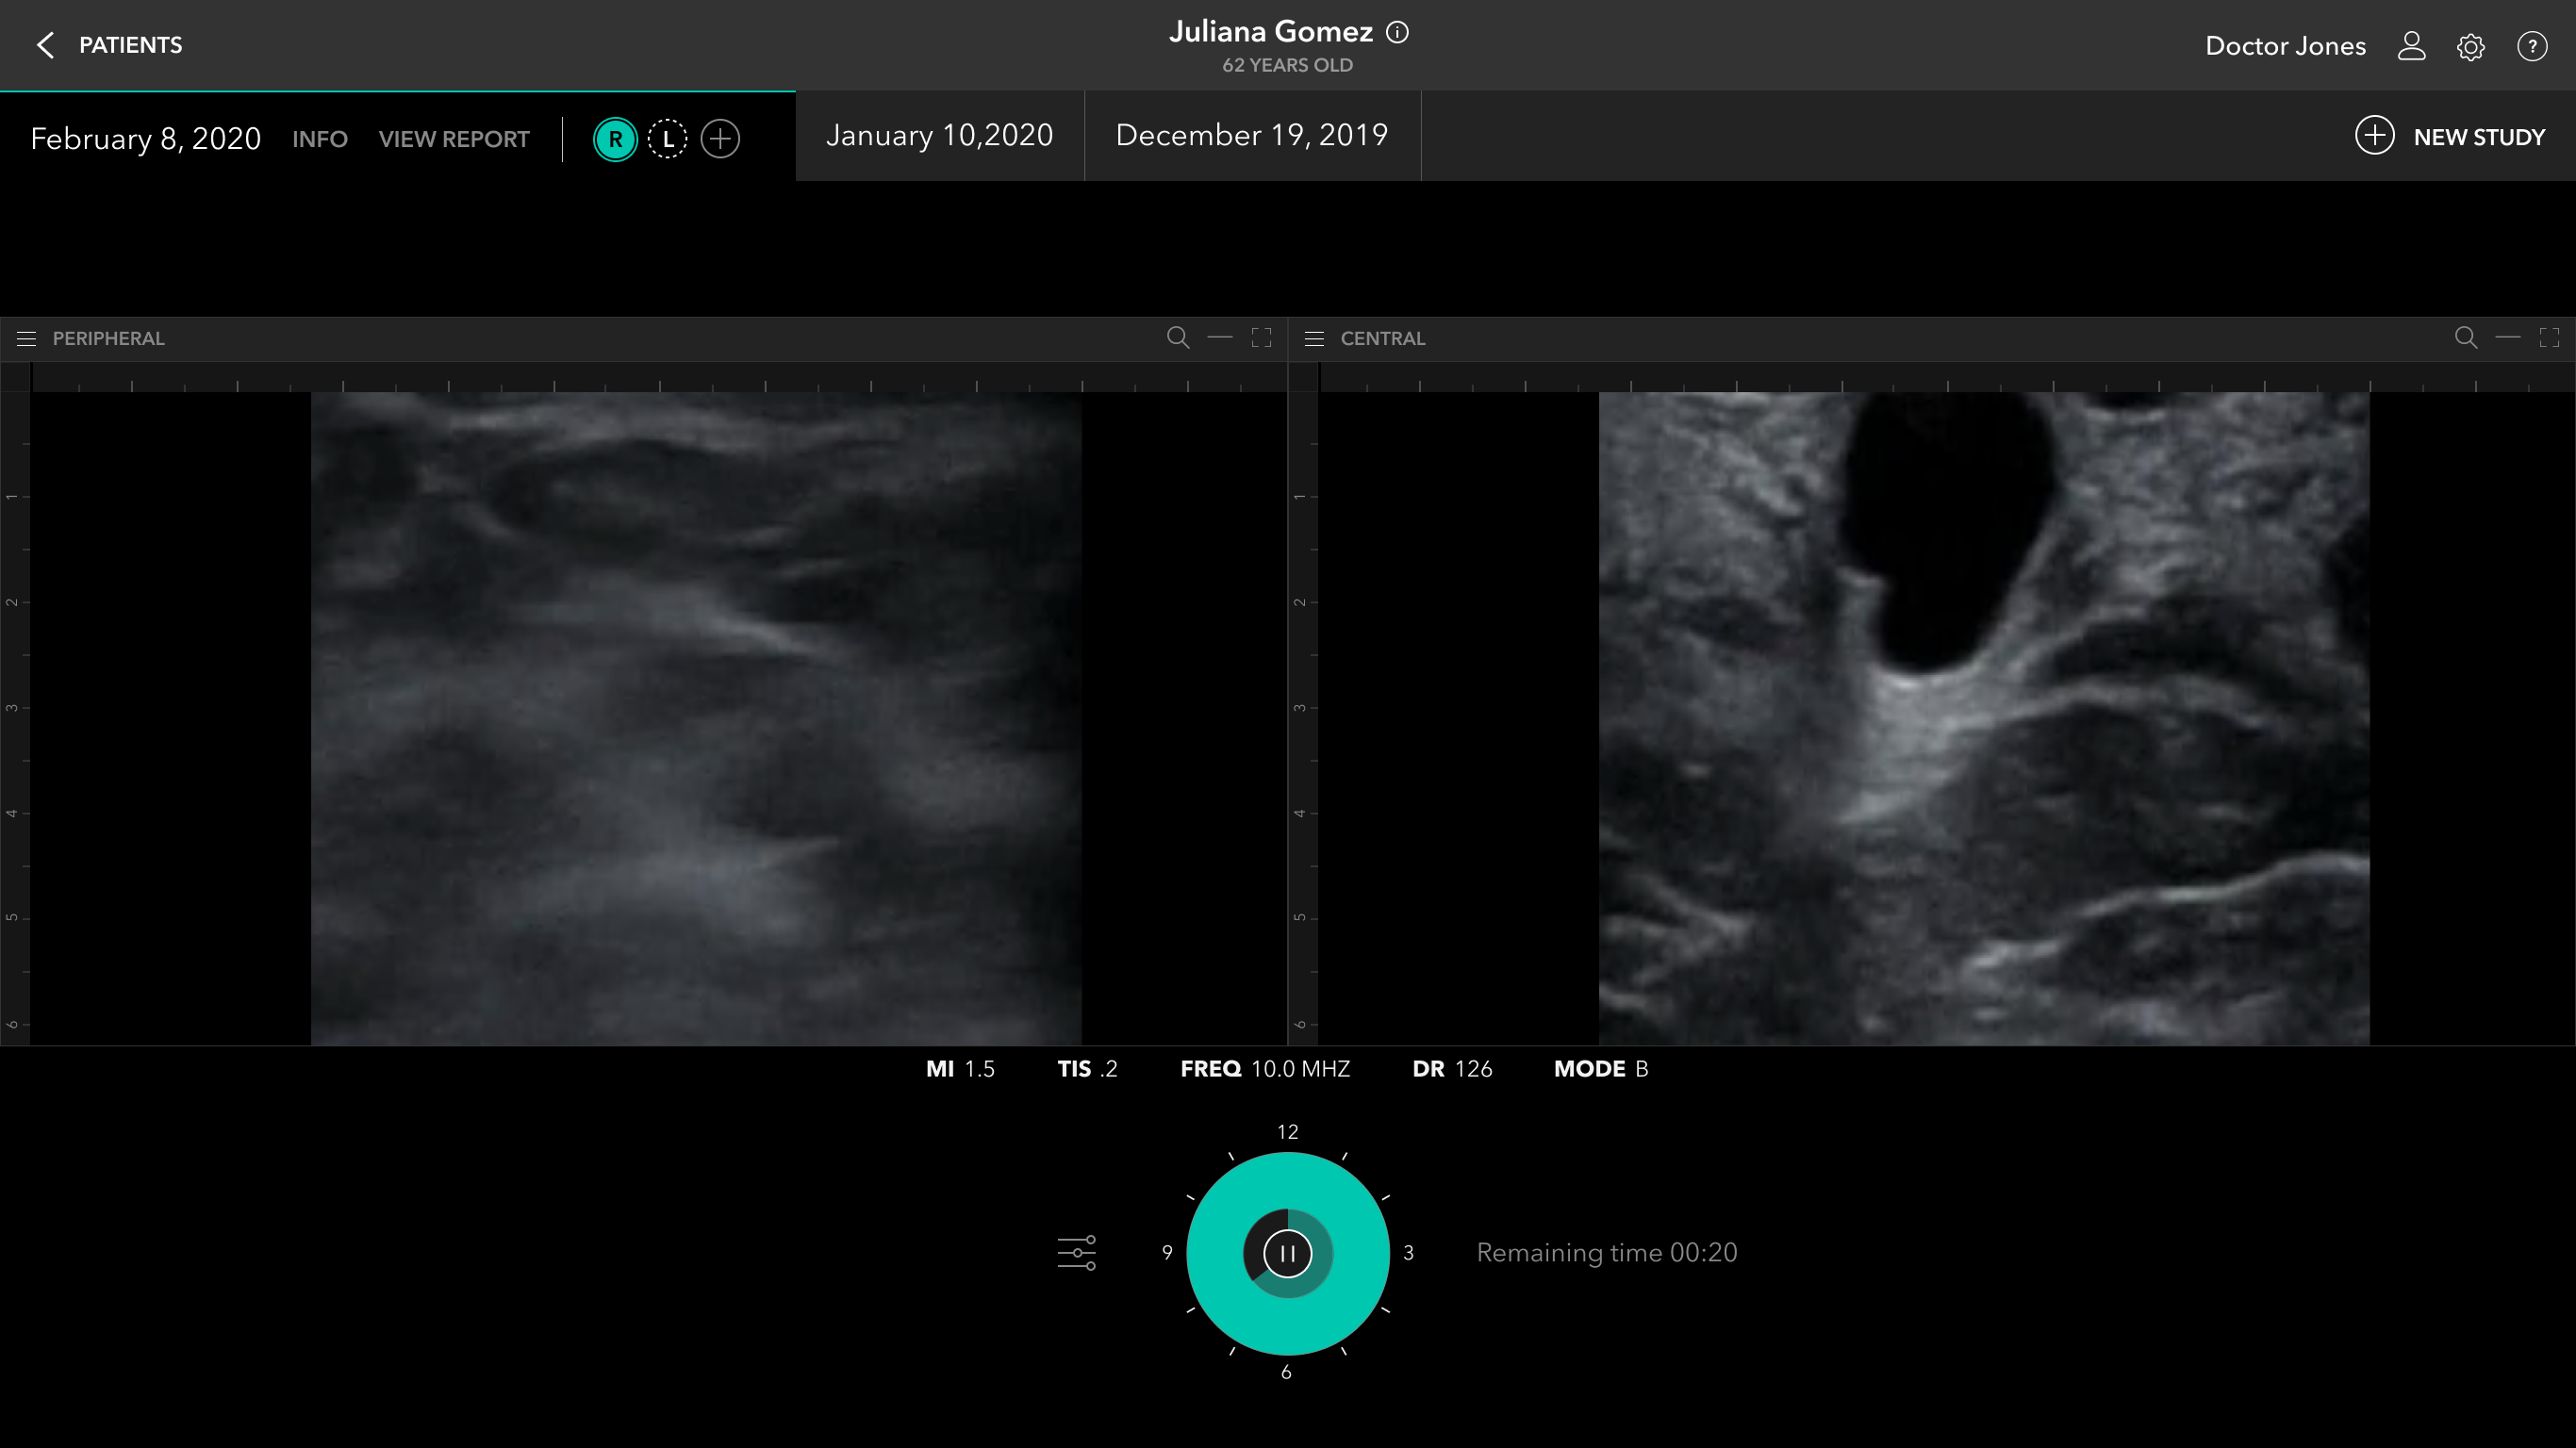

Scan Flow

Post Scan / Labeling And Annotation